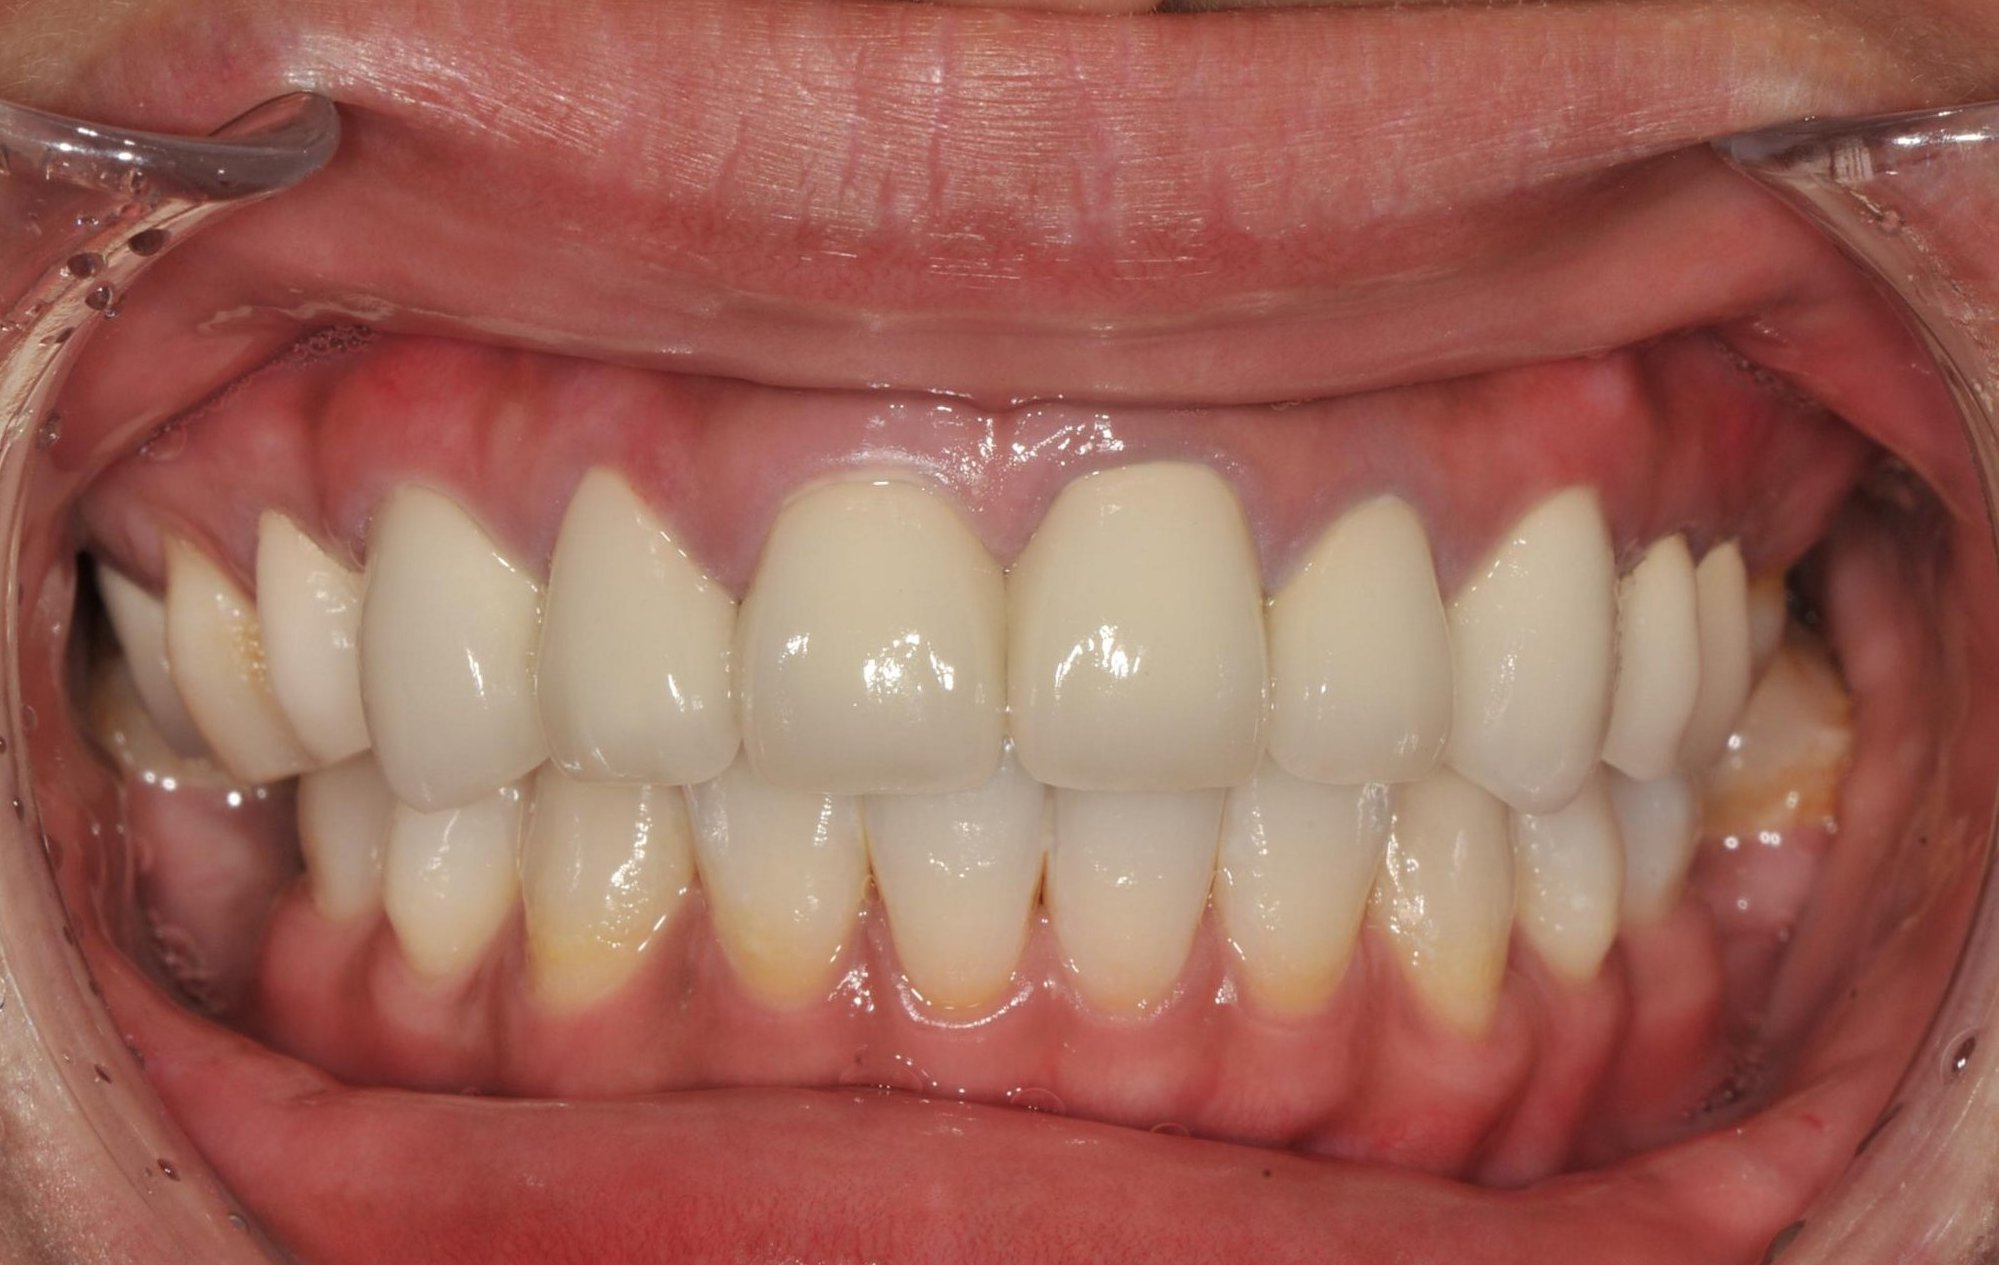

圖九為上頷九顆前牙瓷牙裝戴完成後 , 圖十為咬合面觀

圖九 |

圖十 |

術前、術後比較

術前 |

術後 |